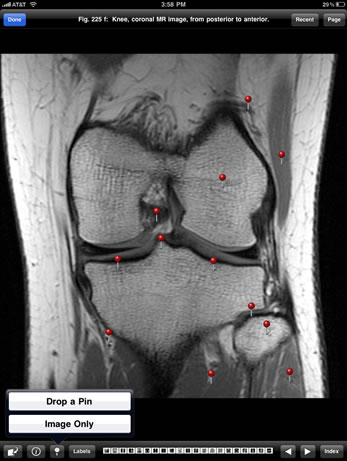

The Imaging Atlas of Human Anatomy, 4th edition, presents a healthy human body as seen via the full range of modern imaging techniques. Content includes images showing cross-sectional views in CT and MRI, nuclear medicine imaging, and more.

Based on the print atlas, written by Jamie Weir, Peter Abrahams, Jonathan D. Spratt, and Lonie Salkowski, this content collection offers a complete view of the structures and relationships within the body through a variety of imaging modalities.